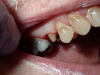

Fig 2. Prepared tooth and margin.

Figure 2

An advantage of using cord technique is that it generally provides an accurate and precise measurement,7,8 physically separating the gingiva away from the prepared margin to allow the clinician to insert light-body material to flow below the margin. Additionally, if a double-cord technique is used, the clinician can leave the bottom cord in place. Moreover, no new equipment is required, and chemicals may not be needed. The clinician needs only the cord and a cord packing instrument. Drawbacks to using cord are the risk of epithelial attachment injury, some pain that may necessitate the use of local anesthesia, a level of technique sensitivity that typically requires practice on the part of the clinician to become skilled, the likelihood of bleeding, and the risk of irreversible gingival injury that may lead to permanent recession.9,10 Figure 2 through Figure 5 show close-up photographs of a prepared tooth and margin, cord being packed, cord in place, and margin after cord removal, respectively.